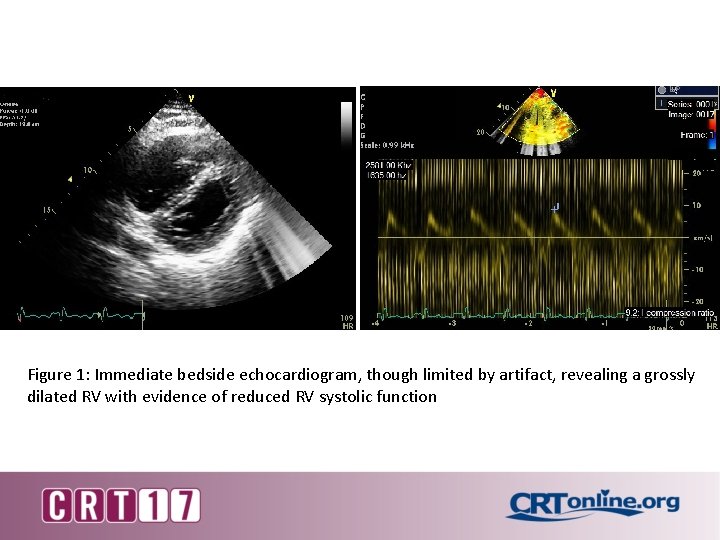

Figure 1: Immediate bedside echocardiogram, though limited by artifact, revealing a grossly dilated RV with evidence of reduced RV systolic function